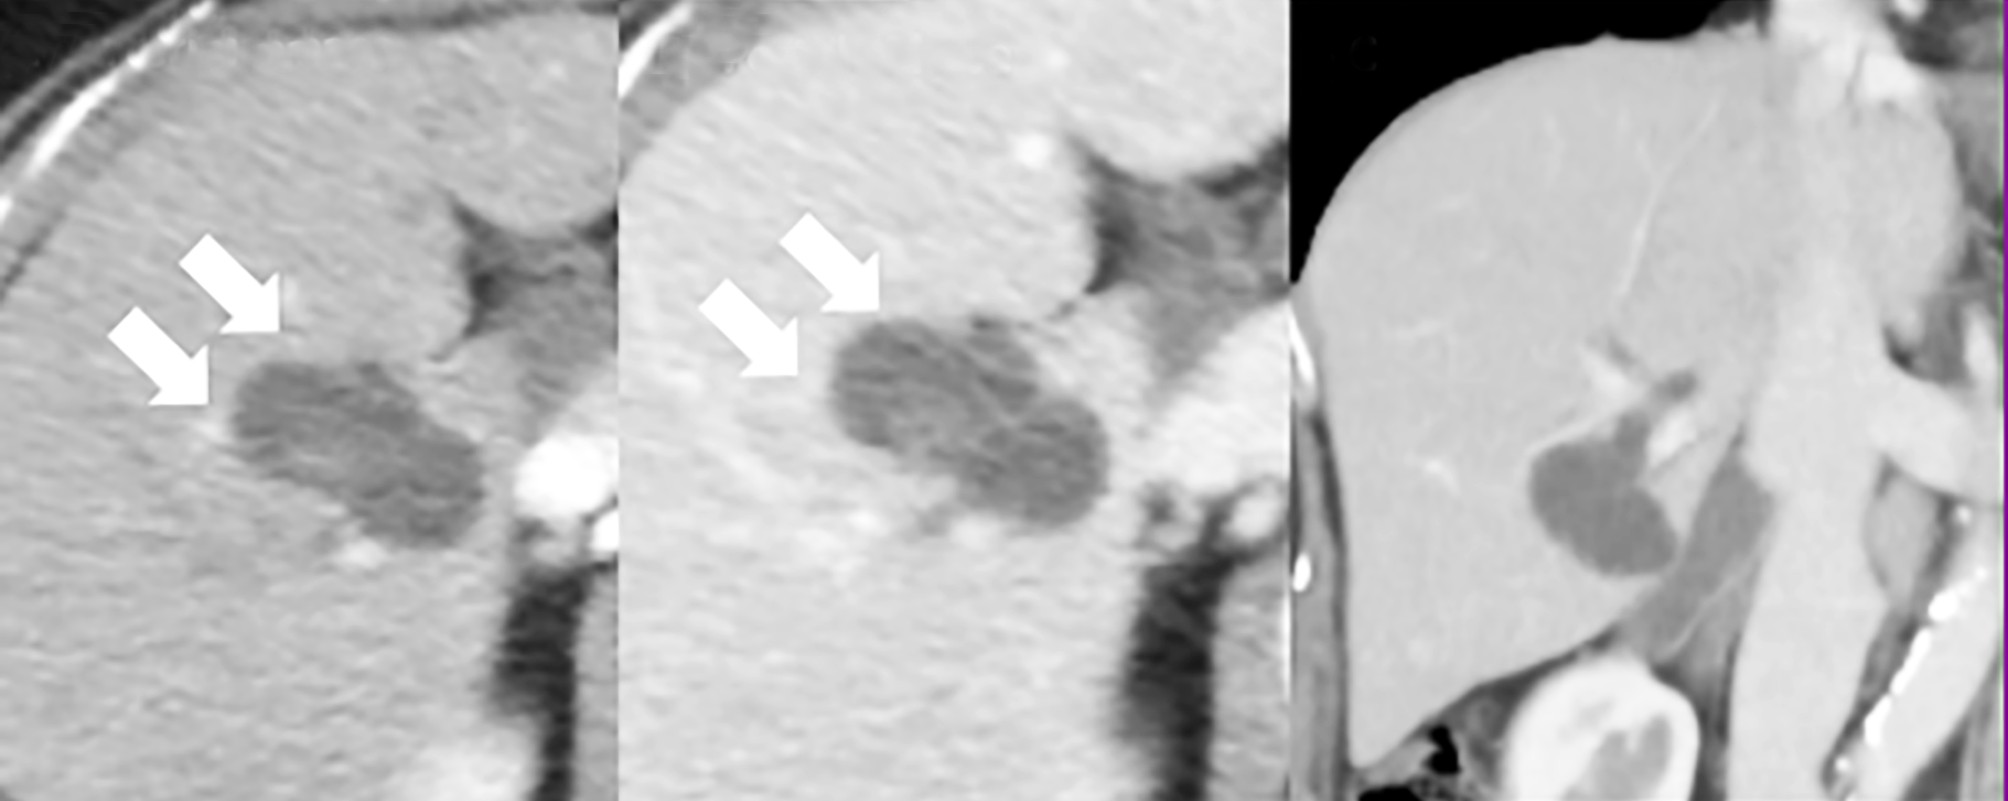

Abdominal ultrasonography identified a space-occupying lesion at liver segments 5 and 6, measuring 30 × 30 mm in diameter, with a mural nodule. Dynamic computed tomography indicated that the mural nodule inside the cyst was slightly enhanced during the early phase; this enhancement was prolonged during the delayed phase (fig. 1 a-c). Magnetic resonance cholangiopancreatography revealed that the tumor was connected to the biliary duct of segment 5 (fig. 2 a, b). Endoscopic retrograde cholangiopancreatography revealed that the intrahepatic bile duct was dilated owing to mucin produced by the tumor and that the tumor was connected to segment 5 of the biliary duct

Figure 1 - Abdominal computed tomography findings. (a) and (b): A multilobular 30- × 30-mm tumor with adjacent lesions detected in liver segments 5 and 6. The arrows (®) indicate where the mural nodule inside the cyst is slightly enhanced during the early phase. This enhancement was prolonged during the delayed phase. (c): This image reveals dilatation of the right hepatic duct